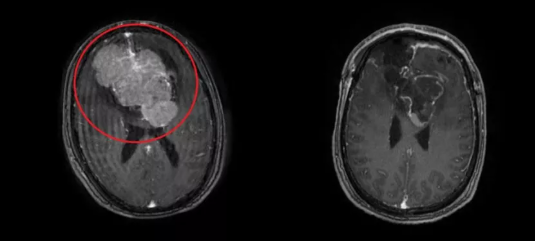

经检查,陈陆馗考虑钟叔颅内病变可能性大,于是安排了颅脑磁共振检查,果不其然,结果显示:双额正中部前纵裂区见一巨大肿块,大小有9.3cm*7.3cm*5.3cm。

根据患者的症状体征及影像学资料,初步判断是巨大脑膜瘤,建议尽早手术治疗。

▲双额正中部前纵裂区巨大肿块(左图),肿块切除后(右图)

7月23日,陈陆馗带领神经外科团队经过近10小时的手术,成功切除钟叔的颅内巨块肿瘤,术后病理显示:化生型脑膜瘤(WHO I级)。